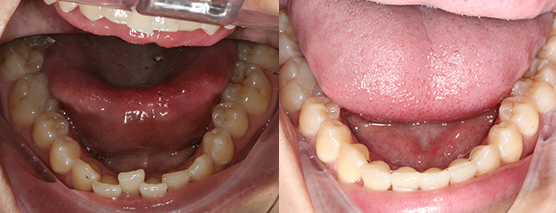

Case examples that can be treated in your practice.

(Cases treated by Dr Andrew Chang using in office aligner solutions)

Before

After